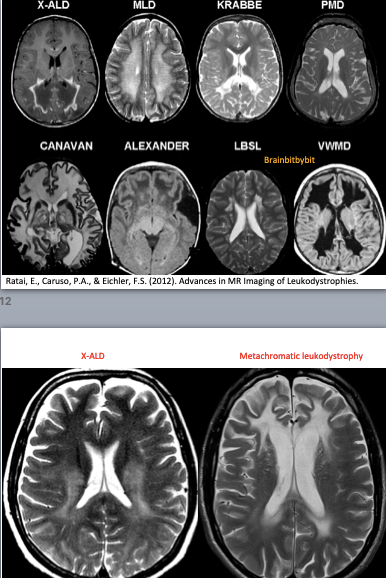

If the myelination pattern does not concur with the calender age, there can be hypomyelination or dysmyelination, meaning that not enough myelin is formed. Leukodystrophy is a term used for rare disorders involving (mainly) white matter with an underlying genetic, metabolic cause and symmetrical involvement as a key MRI finding(47-52). In demyelinating disorders there is destruction of previously formed myelin. The most known and prevalent demyelinating disease is not a leukodystrophy but an inflammatory one: multiple sclerosis, with a specific pattern of (non-symmetrical) white matter abnormalities on MRI located periventricular, in the corpus callosum, juxtacortical and infratentorial (39).